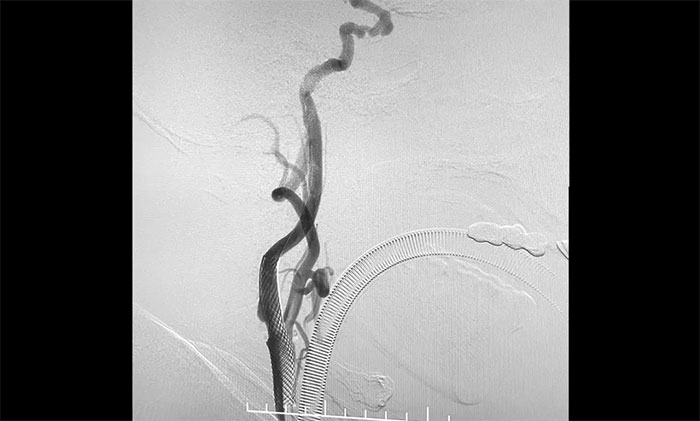

術中,席剛明教授、王貴平博士先對左頸內動脈起始段重度狹窄處進行開通治療,在保護傘下經(jīng)過多次球囊擴張后,順利釋放支架于左頸內動脈起始段至左頸總動脈末段,造影見狹窄明顯改善,順利開通血管。

接下來,左頸內動脈海綿竇段、床突段多發(fā)動脈瘤處理極具挑戰(zhàn)。由于C5、C6、C7段血管極度迂回曲折,類似“N”形,從C4、C5到C6之間的血管約成45°銳角,從C6至C7之間又是約30°銳角,可謂“山路十八彎”,而導絲又是極軟,每向前推進一毫米,都非常艱難。這種介入手術對術者的技術要求非常高,如果支架貼合不好,打開不良,還需要用導絲蠕動“按摩”,讓支架重新回到血管壁上。